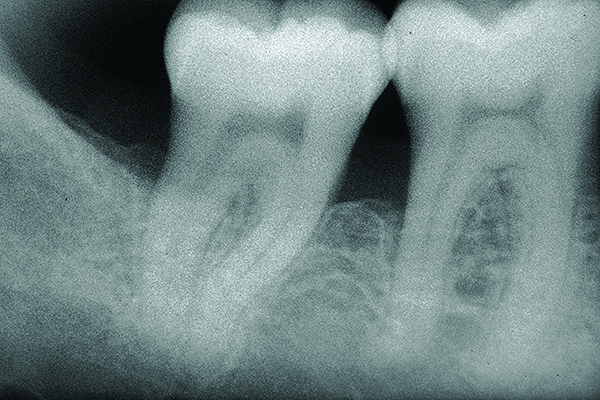

Periodontal regeneration to reverse bone loss can be used successfully in certain Class II furcation defects to eliminate the furcation bone loss or reduce the involvement to a Class I defect, creating an environment more conducive to long-term stability and maintenance (Figure 9 and Figure 10).22-25 Identifying furcation involvement and intervening with early treatment can enhance the long-term prognosis.26

Fig 9. X-ray shows bone loss on the distal aspect and in the area of the furcation of tooth No. 31.

Figure 9

Fig 10. Postoperative x-ray depicts bone fill of the defect 2 years after regenerative therapy.

Figure 10